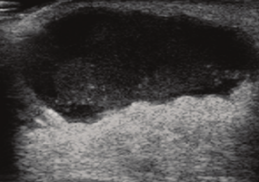

• *Hypoechoic mass**

• Ill-defined

• Hyperechoic angular margins

• Spiculations or thick halo

• Ductal extension

• Branched pattern

• Microcalcifications

• Vascular

Non-compressible

• *Acoustic transmission**

• *-** Post shadowing (grade 1)

• Post enhancement (grade 3)